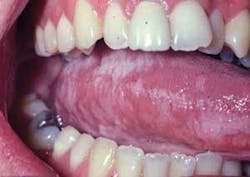

As you begin your exam of Richard's tongue, you notice that he has plaque and white lines that have a shaggy appearance on the lateral borders of the tongue (see Figure 1). Richard has noticed the white appearance and tells you that he has tried to brush the plaque away without success. With Richard's health history and a biopsy, it is determined that he has oral hairy leukoplakia.

Perioral and intraoral characteristics: HL is asymptomatic unless there is a candida infection in conjunction with HL, causing the characteristic burning sensation associated with candidiasis. The hygienist or dentist may be the first individual to notice the clinical signs related to suppressed immune function. The nonpainful, white, and corrugated/shaggy plaque appear as accentuated folds on the lateral borders of the tongue and are very characteristic of HL. The lesions are usually bilateral, but may be unilateral as well (see Figure 2).